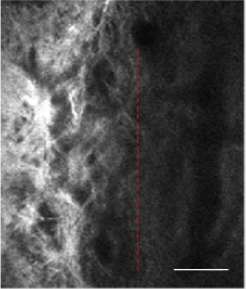

(Figure 1) illustrate the region of the TM in the normal condition. According to the imaging principle of TPM, the zones absent of signals agree with the aqueous-filled spaces within the AOS, and the collagen fibres of the TM can be clearly seen. The TM beams seem to be heterogeneous with depth increases. Additionally, it is easy to identify the superficial meshwork, which is a filter comprising a network of connective tissue. There are dark regions, which are shown as gaps between these beams and which allow the drainage of AH.

Figure 1: The image was taken at a depth of 200μm below the corneoscleral limbus. The left of red dotted area is the trabecular meshwork channel tissue.